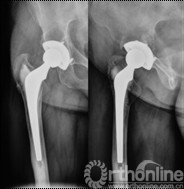

女,50岁,因髋关节发育不良继发骨关节炎行混合性固定(非骨水泥髋臼,骨水泥柄)THA手术。术后6年4个月发现腹股沟部渐增大、无痛性包块;体查:关节活动正常,腹股沟处可触及一10mm×10mm大小、质中等、移动度差、无触痛包块。超声检查提示右髂窝包块,呈强弱不等回声,大小约12cm×10cm,边界清楚。Harris评分88分。X线片示髋臼顶部DeLee和Charnley II区不规则低密度透光区,无连续骨小梁(图5)。CT片示髋臼假体上方DeLee和Charnley II区骨溶解区,DeLee和Charnley I、III区髋臼假体骨长入固定(图6)。WBC6.7×109/L,中性64%,ESR 28mm/h,CRP 8.34mg/L。聚乙烯线性磨损率为0.17mm/年,容积磨损率为543.42mm3/年,骨溶解区面积为412.52mm2。诊断:THA术后髋臼假体周围局灶性骨溶解(假体稳定)伴假性瘤样形成。

图6 CT片示髋臼假体上方DeLee和Charnley II区骨溶解, I、III区骨长入固定,髂窝内假性瘤样肉芽肿(箭头所示)

图11 术后2年随访,CT扫描显示髋臼骨溶解区新生骨组织替代,骨溶解区骨长入良好,髋臼骨长入固定